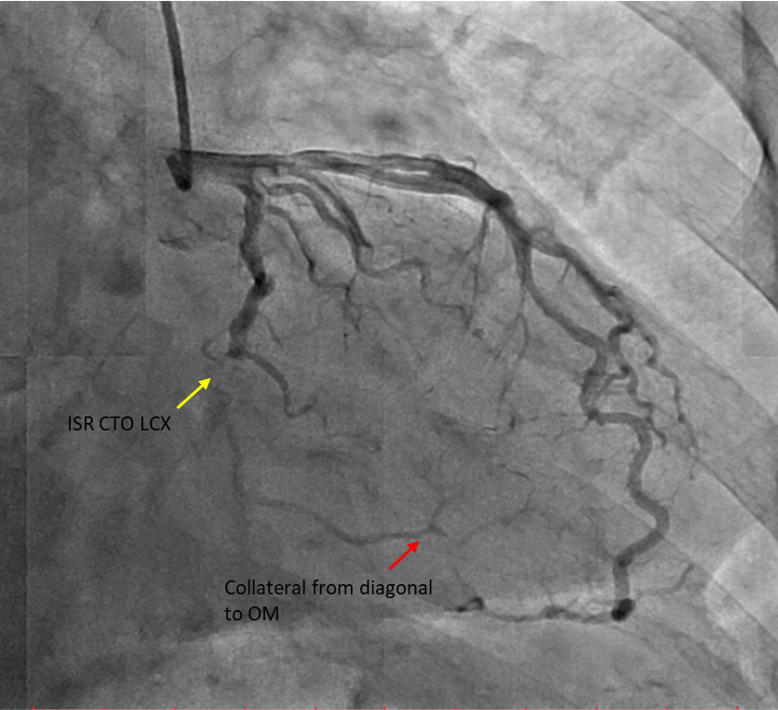

Diagnostic CAG:Left main stem: normalLeft anterior descending artery: proximal 30% stenosis, mid myocardial bridging, diagonal branch giving collateral to OM branchLeft circumflex artery: stent in distal LCX with ISR type IV 100% occlusionRight coronary artery: Dominant, mid 40-50% stenosis, PLV branch giving collateral to OM branch

Percutaneous coronary intervention (PCI) was performed via transradial approach with 6 Fr radial sheath. Left coronary system was engaged using EBU 3.0 6 Fr guiding catheter. We decided for antegrade approach. Initial attempt with Fielder XT-A wire with a microcatheter support failed to cross the in-stent restenosis (ISR) lesion. We escalated to Asahi Gaia Second wire and successfully crossed the lesion to OM branch. Subsequently, wire was exchanged to a workhorse wire Runthrough Floppy via microcatheter. Lesion site was first predilated with a semi-compliant balloon Pantera Pro 2.0x 15 mm. Then, IVUS was passed down which showed previous stent site undersized, vessel size distal LCX of 4.0 mm. We further predilated lesion site with scoring balloon Scoreflex Trio 3.5x15 mm, up to 22 atm. Lesion site was acceptably prepared, then Paclitaxel drug-coated balloon Prevail 4.0x25 mm was deployed at nominal 6 atm for 60 seconds. Repeated IVUS run showed good stent apposition with MSA of 9.5mm2 proximally and 6.6mm2 distally. Final fluoroscopic shot showed good result with TIMI 3 flow, no stent edge dissection. Patient was symptom-free after procedure and discharged the following day.